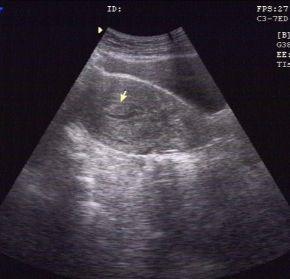

一位24岁,无月经周期、经期和经量的改变。常规体检妇科超声描述:宫腔内见高回声区8mm×5mm,提示:子宫内膜息肉。

子宫内膜息肉的无创检查,首选妇科超声检查,推荐经阴道超声(有*生活性**史的女性)或经直肠超声(无*生活性**史的女性)。一般妇科超声检查的时间选择月经周期的第5-7天(早卵泡期)为最佳。但即使超声有上述提示子宫内膜息肉,并不等于确诊。